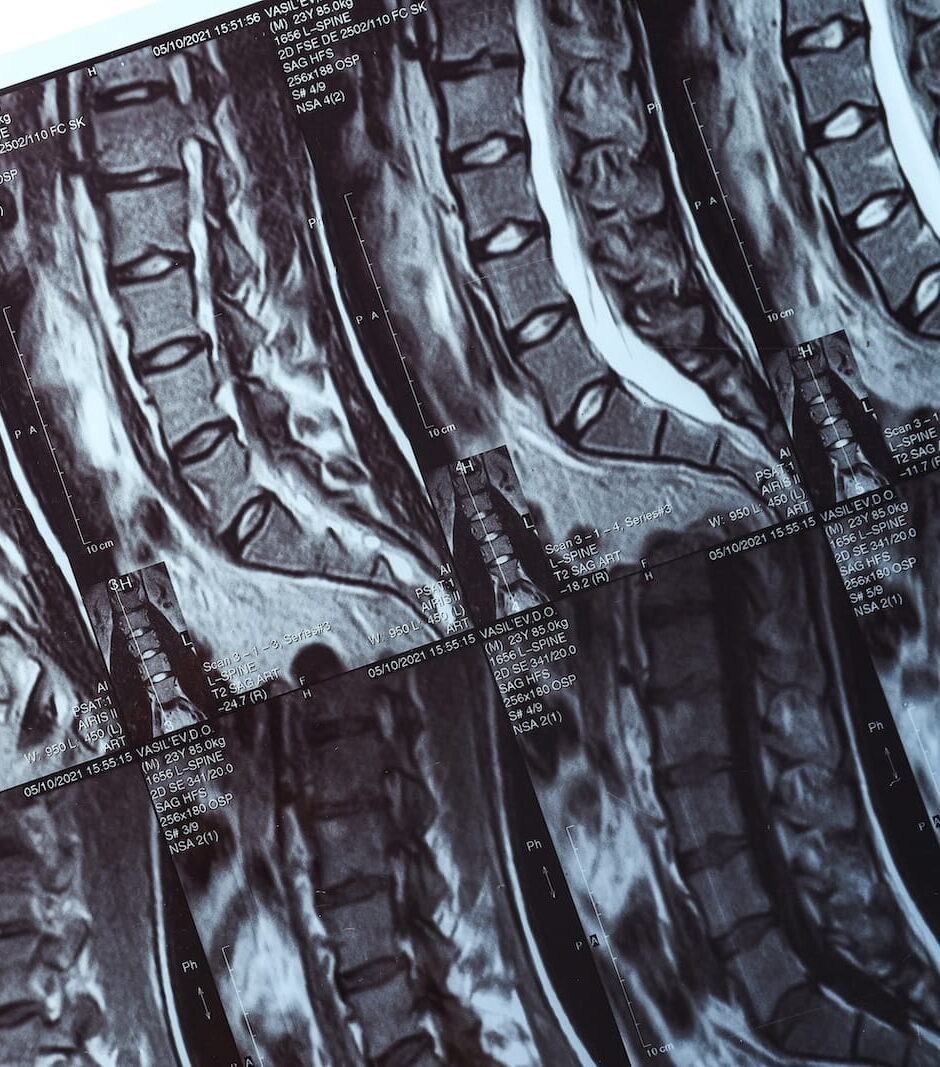

• imaging that matches their symptoms